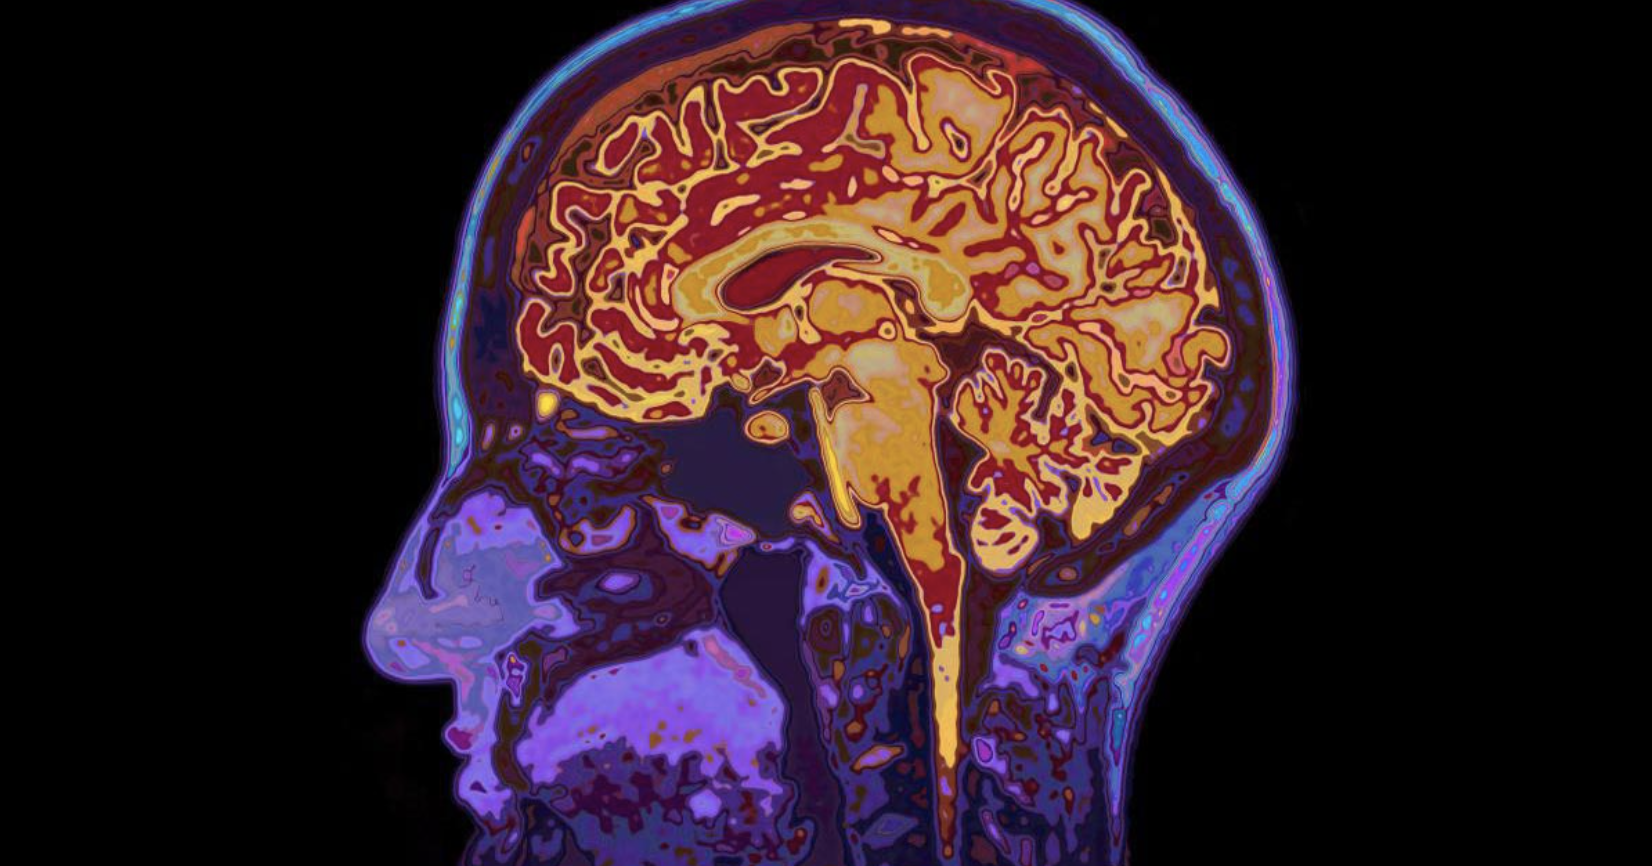

In a shocking landmark study, the severe danger to brain health presented by COVID-19 Spike protein was exposed last week by a cross-disciplinary research team of 30 doctors.

Our results revealed the accumulation of the spike protein in the skull marrow, brain meninges, and brain parenchyma. The injection of the spike protein alone caused cell death in the brain, highlighting a direct effect on brain tissue. Furthermore, we observed the presence of spike protein in the skull of deceased long after their COVID-19 infection, suggesting that the spike’s persistence may contribute to long-term neurological symptoms.